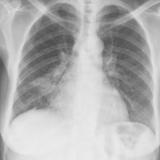

Gallery Lobar Collapse

Lobar Collapse

LUL Collapse

Album: LUL Collapse

LLL Collapse

Album: LLL Collapse

RLL Collapse

Album: RLL Collapse

RUL Collapse

Album: RUL Collapse

RML Collapse

Album: RML Collapse